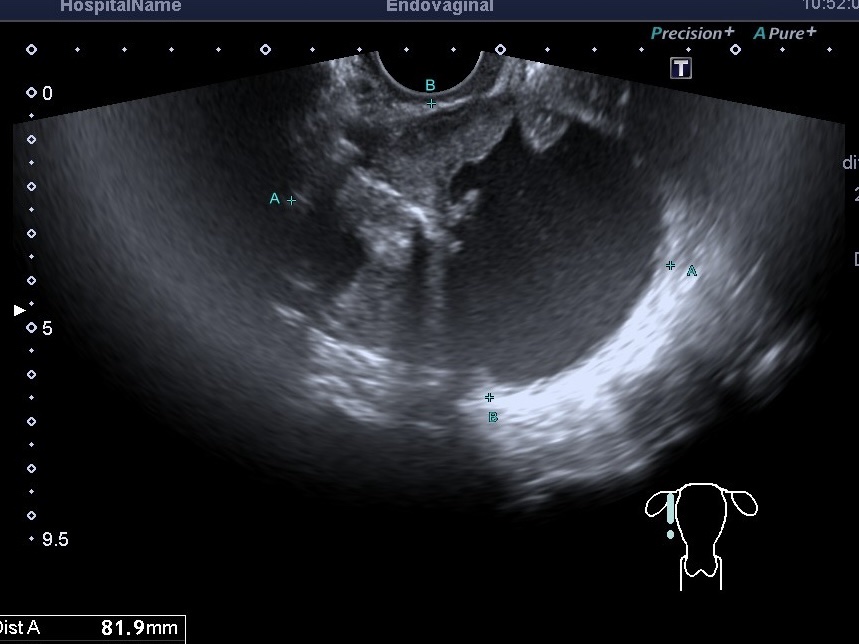

Патології малого таза трапляються дуже часто, і головне завдання лікаря — не пропустити утворення в цій області . Останніми роками...

Ера Інтернету, доступності інформації дали свої позитивні наслідки,особливо молоді люди почали більше приділяти увагу своєму здоров’ю,профілактиці. УЗД малого тазу в...